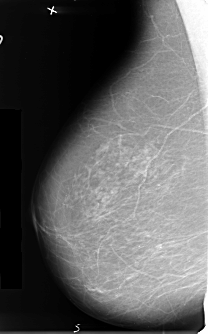

B_3412_1.LEFT_MLO

LEFT_CC LINES 4608 PIXELS_PER_LINE 3120 BITS_PER_PIXEL 12 RESOLUTION 50 OVERLAY

LEFT_MLO LINES 4816 PIXELS_PER_LINE 2728 BITS_PER_PIXEL 12 RESOLUTION 50 OVERLAY

FILE: B_3412_1.LEFT_MLO.OVERLAY

TOTAL_ABNORMALITIES 1

ABNORMALITY 1

LESION_TYPE MASS SHAPE ROUND-IRREGULAR-ARCHITECTURAL_DISTORTION MARGINS SPICULATED

ASSESSMENT 5

SUBTLETY 5

PATHOLOGY MALIGNANT

TOTAL_OUTLINES 1

FILE: B_3412_1.LEFT_CC.OVERLAY